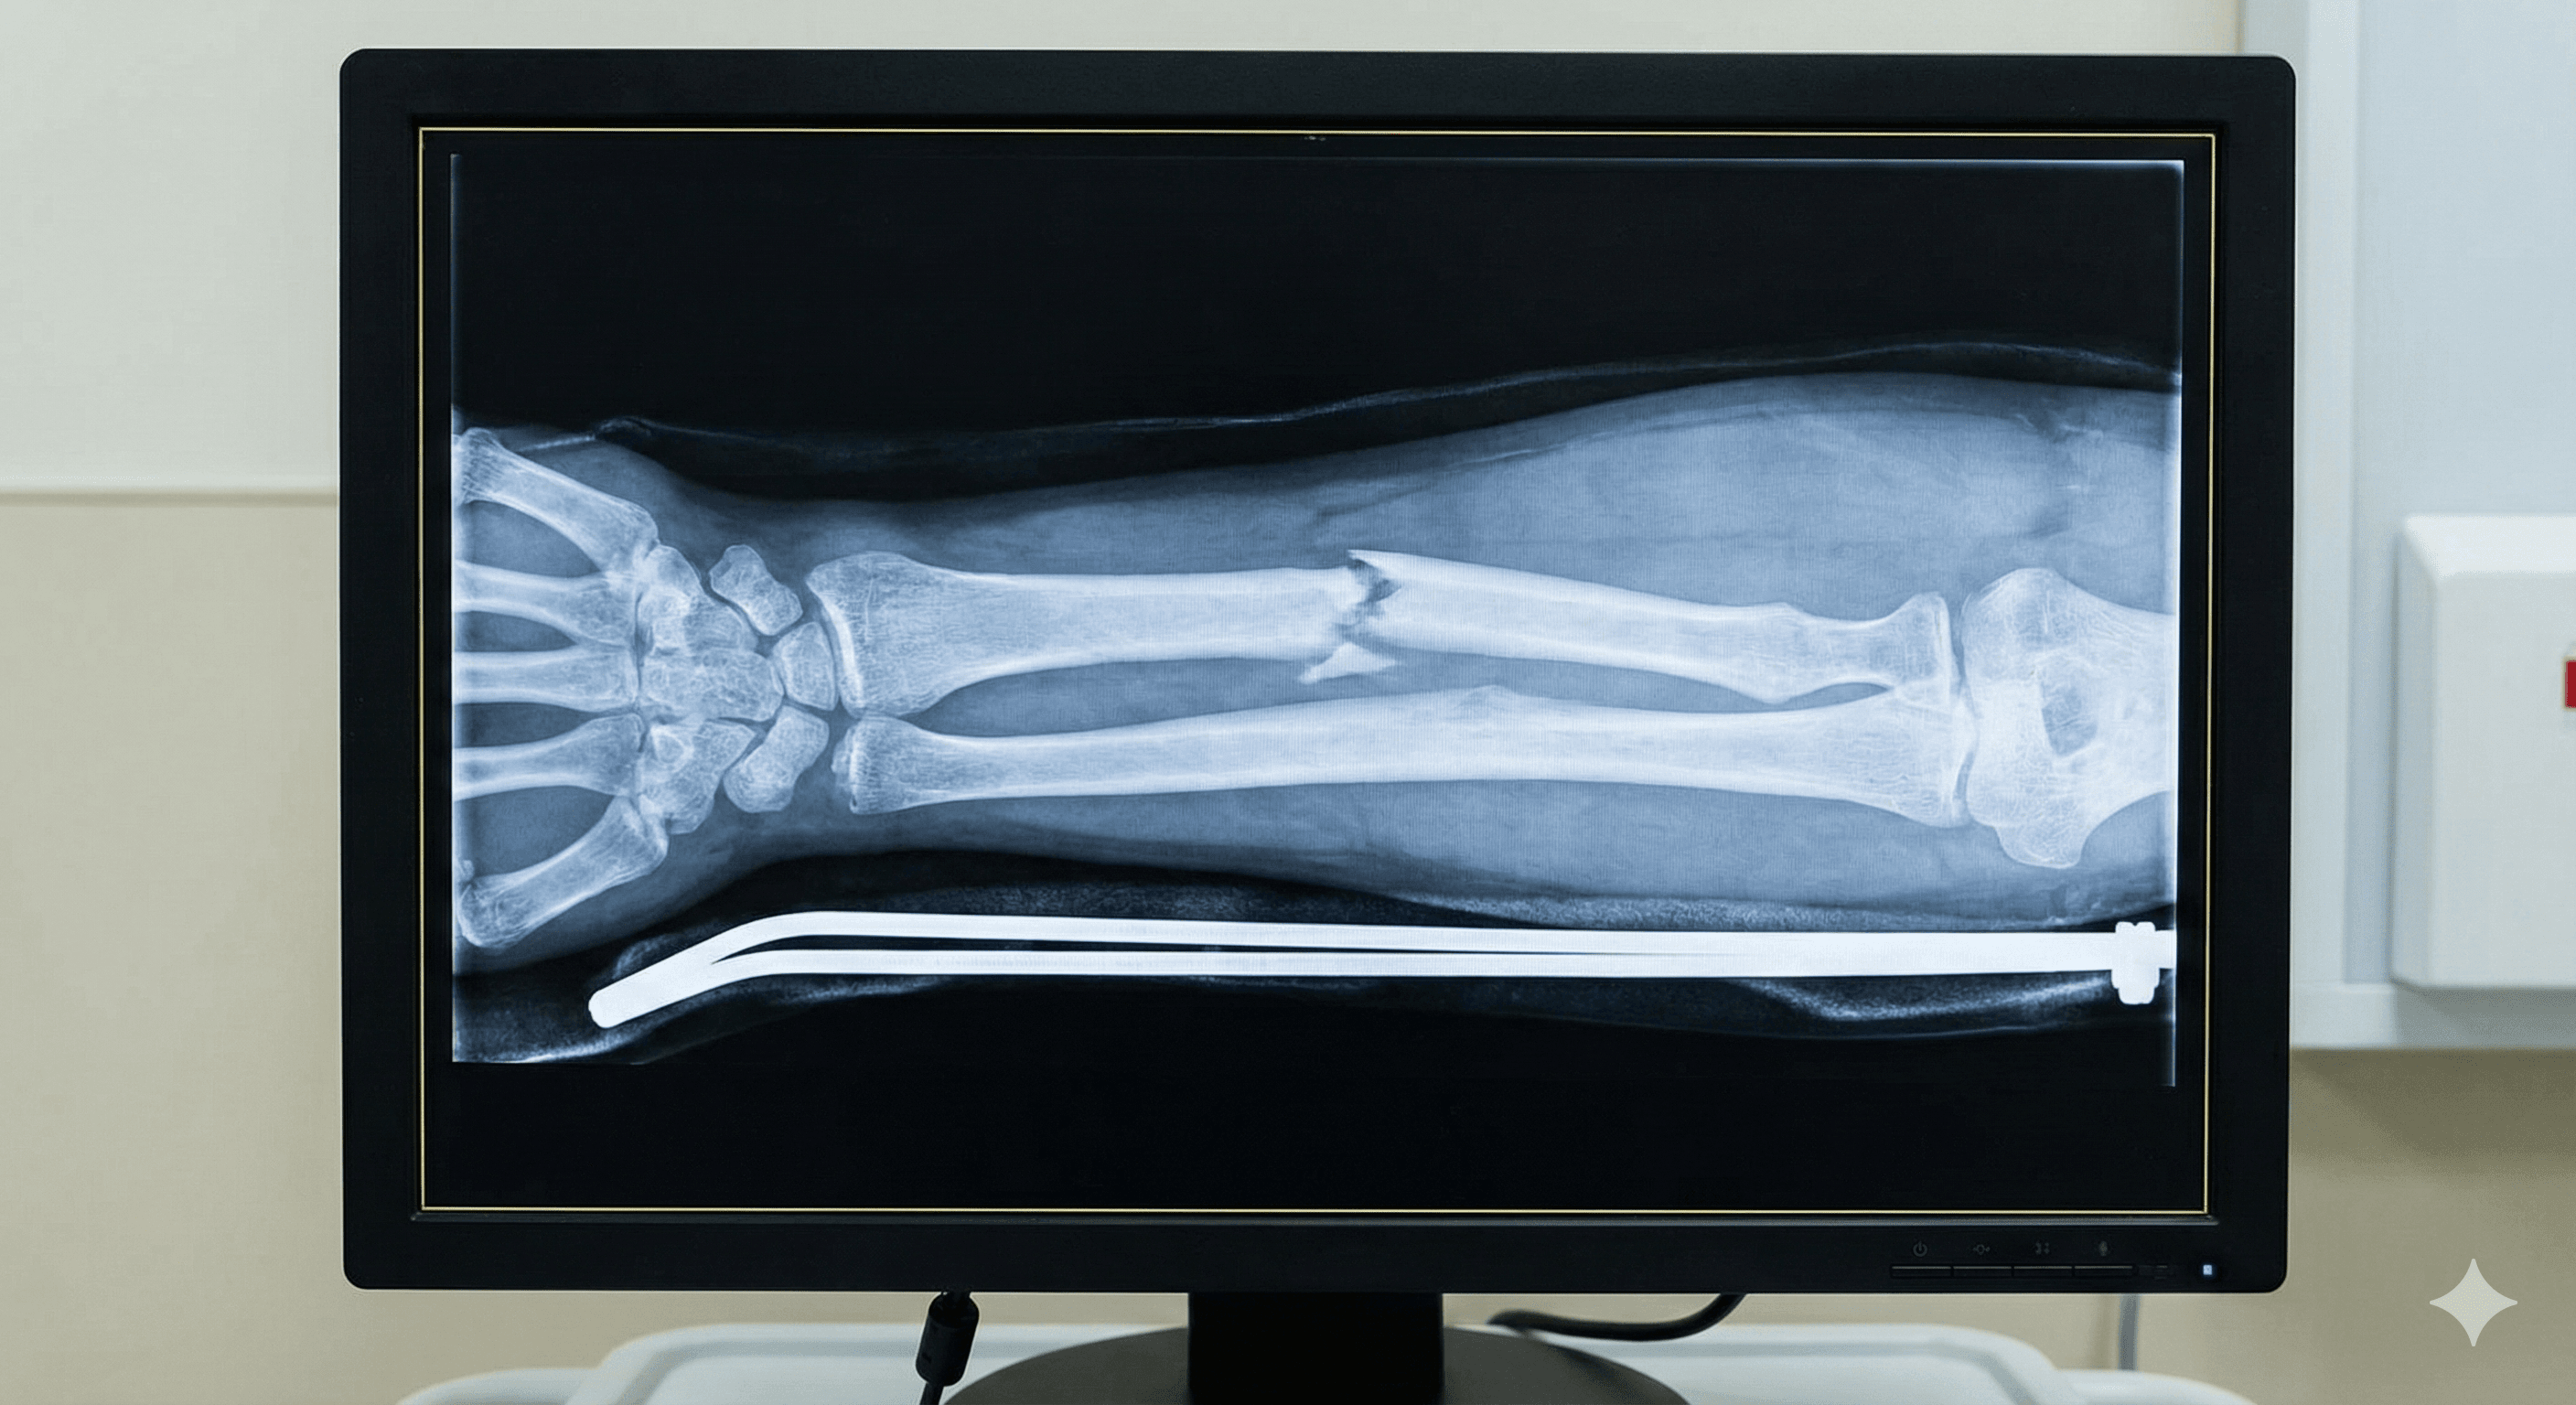

Ruptura parcial o total de un hueso, generalmente causada por traumatismos fuertes, caídas o debilidad ósea.